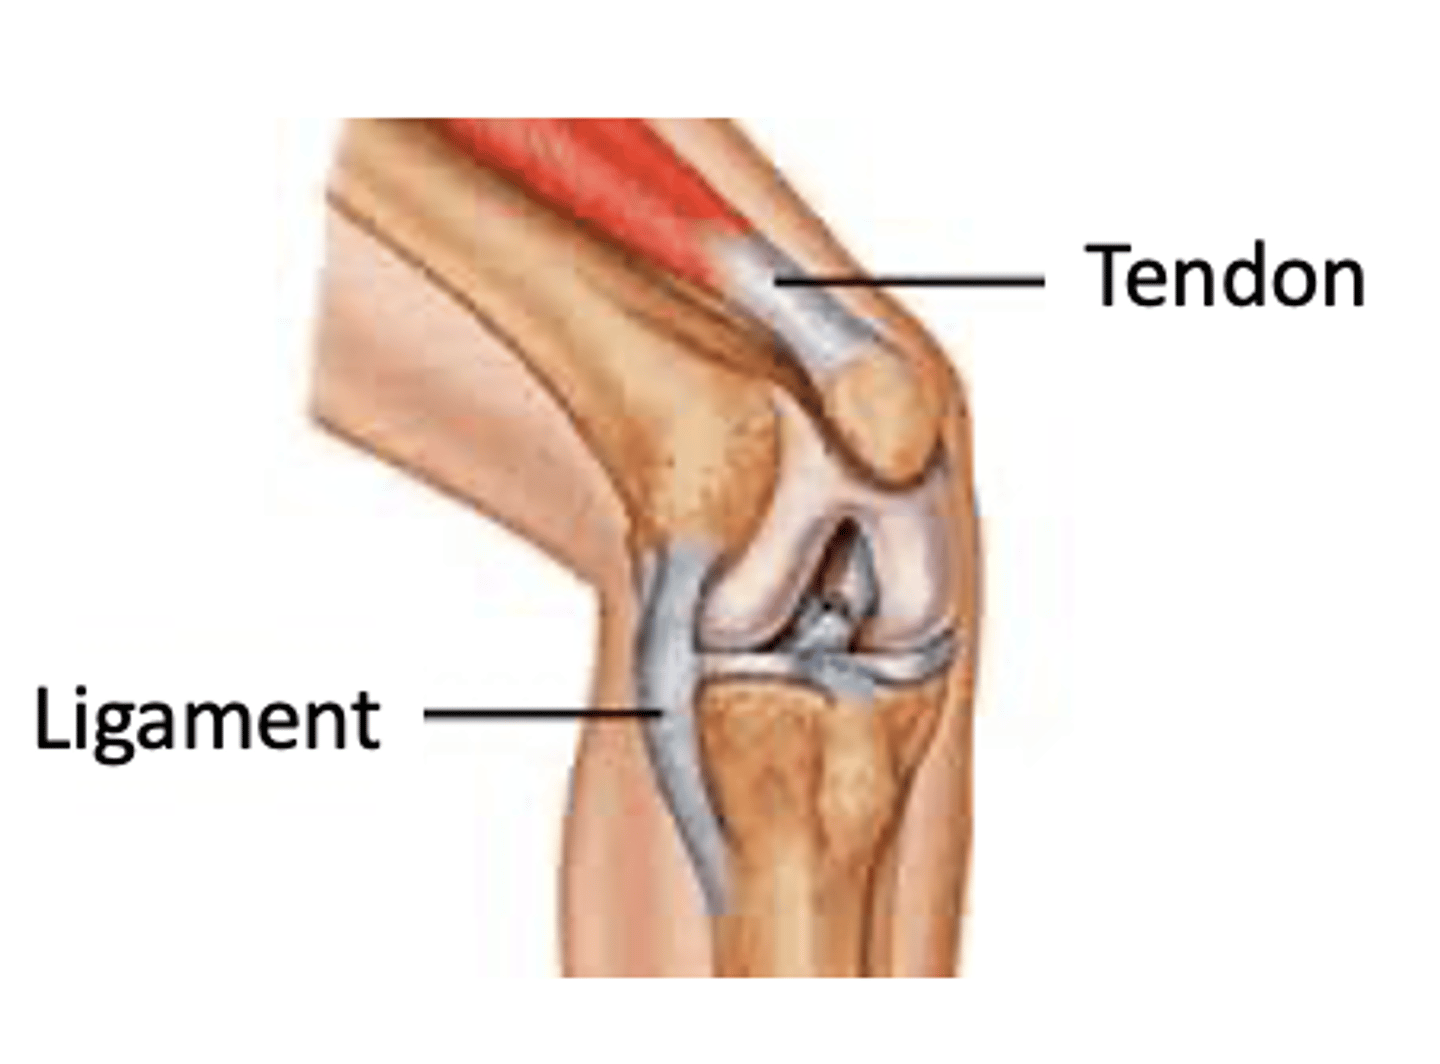

Ligaments and tendons

have a limited blood supply

(Implication for healing?)

Dense regular connective tissue

-- Inelastic collagen fibers

-- High tensile strength